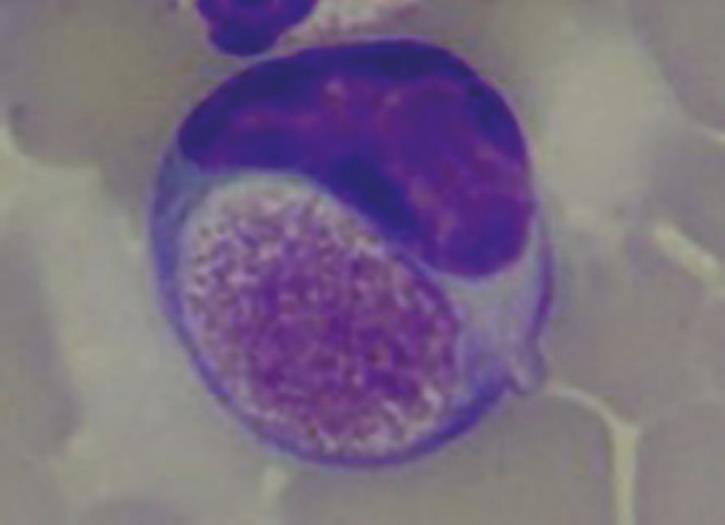

Foa-Kurloff cells (Fig. 6) represent one last haematological feature of this species. Foa-Kurloff cells are mononuclear leukocytes (often lymphocytes, rarely monocytes) with inclusion bodies (Kurloff bodies), which should not be mistaken for intracellular pathogens, due to their appearance. They can make up 3-4% of the leukocytes.

A particularly high number of these inclusion bodies is described during pregnancy and correlates with the oestrogen level. They are most likely equivalent to the killer cells in other mammals and provide a barrier between foetus and mother.

- Fig. 6: Foa-Kurloff cell with inclusion body of up to 8 µm in size